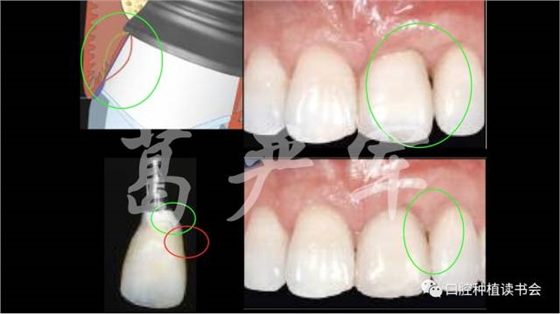

病例一,右上1缺失,在種植臨時修復(fù)期間,通過臨時冠的塑形,在正式修復(fù)后達(dá)到了比較令人滿意的治療效果。

病例二,右上12缺失,在長達(dá)半年的種植臨時修復(fù)期間,五次調(diào)整臨時修復(fù)體的穿齦外形,但幾乎沒有對粘膜邊緣的位置及右上1、2之間齦乳頭高度產(chǎn)生任何影響,正式修復(fù)后的美學(xué)效果也很差。

在我們了解了上述內(nèi)容之后,我們再回頭看開篇筆者提到的兩個病例,這兩個病例在缺牙數(shù)目、軟硬組織缺損量、種植時機(jī)、植入的三維位置、植體規(guī)格、軟組織塑形的具體方法等諸多方面存在差異,兩個病例通過調(diào)整臨時冠穿齦輪廓進(jìn)行塑形后的牙齦形態(tài)有如此大的差異也就不足為奇了。